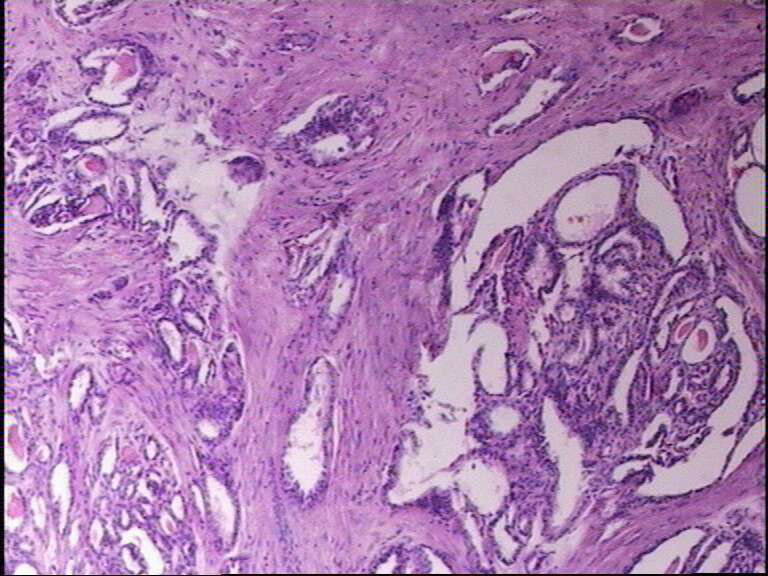

女43岁,甲状腺肿物

就目前的切片看本例没有形成明确的以纤维结缔组织为轴心的乳头结构,前15张图更是连乳头状癌特有的核的表现(核拥挤、核沟、核内假包含体、毛玻璃核等)也不明显,而后传的7张图中核的改变都比前15张图中要明显,个人绝得诊断乳头状癌缺乏重要依据(1)明确的乳头结构(2)核拥挤、核沟、核内假包含体、毛玻璃核,所以希望重取材,多切片搜索可靠的诊断依据再下结论。

乳头状癌:

通过所给图片具备了乳头状结构,也有了核的一些特征,虽不典型:1、核椭圆形,2、核拥挤重叠,3、核上下分层,4、核沟等,可以诊断乳头状癌。

在传几张

• 图1

• 图2

• 图3

• 图4

• 图5

• 图6

• 图7